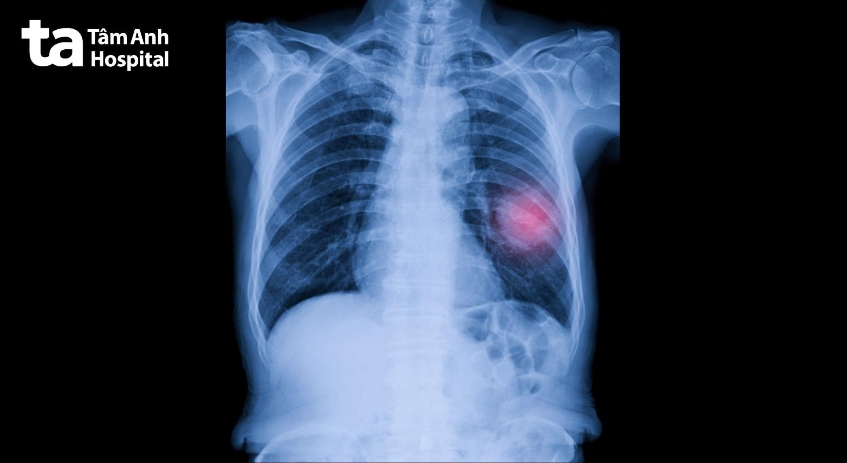

Mô phỏng khối u phổi (màu hồng) trên hình ảnh X-quang phổi.